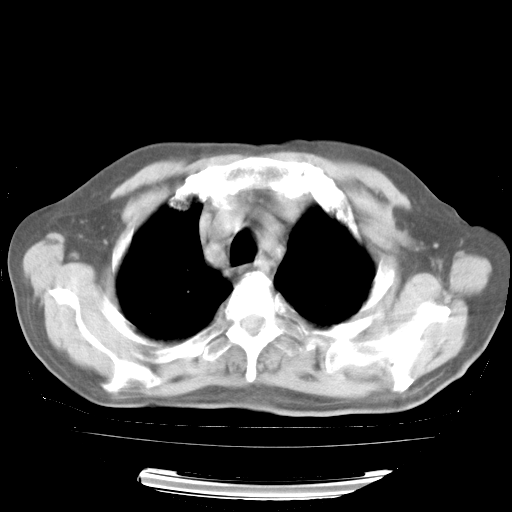

4月28日肺部CT——再次出现类似去年5月9日——透光度降低,“间质性”改变。

4月28日肺部CT